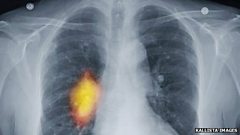

Research 'changing the way cancer is treated'

Duration: 06:57